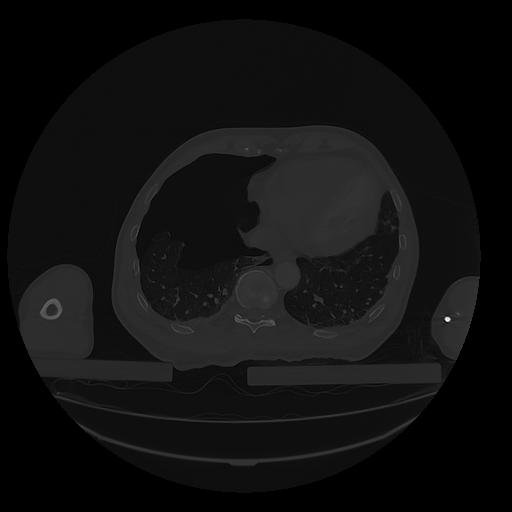

31 PULMON,CE,Vol,1.0,PULMON,,